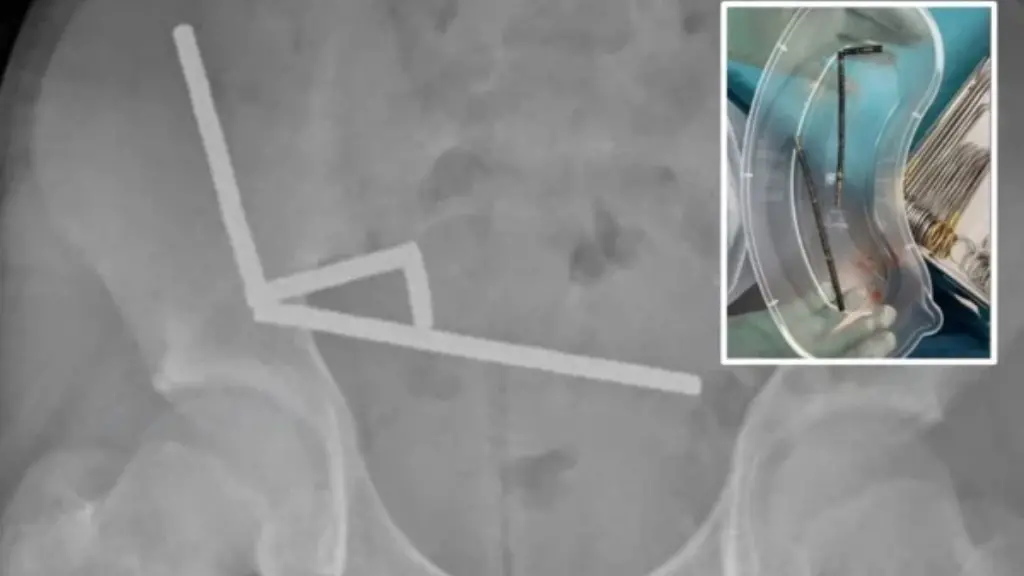

Fotot me rreze X zbuluan katër vargje magnete të shpërndara në pjesë të ndryshme të zorrëve të djaloshit. Pasi futën në sistemin tretës, pjesët e vogla metalike u lidhën ndërmjet tyre.

Gjatë operacionit u vërtetua që vargjet e magnete nga zorra e hollë dhe nga zorra e verbër ishin tërhequr pranë njëri-tjetrit, duke shtypur inde të mesme, shkruan sciencealert.

Kjo çoi në ndërprerjen e furnizimit me gjak dhe vdekjen e disa pjesëve të zorrëve – gjendje e njohur si nekrozë si pasojë e presionit.